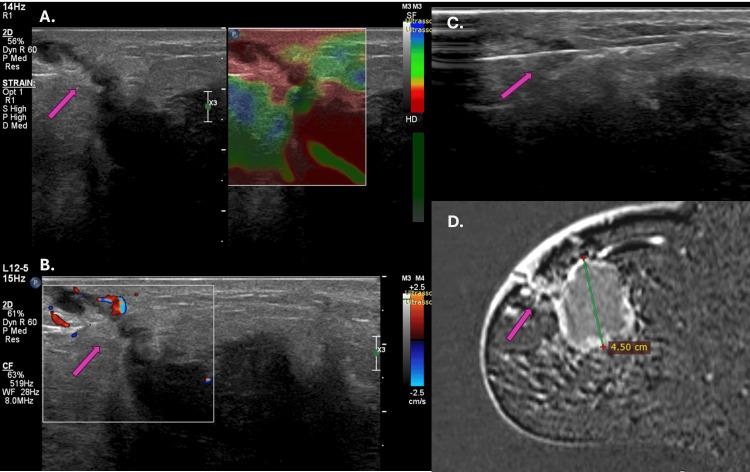

Background Observing patients submitted to percutaneous biopsy at our service who had post-biopsy breast magnetic resonance imaging scans for breast carcinoma staging, we observed tumor extension through the biopsy tract in some lesions, compromising skin and subcutaneous tissue. This study aimed to evaluate tumor extension through the biopsy tract in patients diagnosed with breast carcinoma undergoing neoadjuvant chemotherapy with a radioactive seed marker to locate the original tumor area by retrospectively analyzing MRI, ultrasonography, and histological reports. Methods We evaluated tumor extension through a biopsy tract in consecutive patients included in a prospective observational study protocol to assess the applicability of radioactive seed localization before breast surgery. Sixty-two patients included in the radioactive seed protocol were retrospectively evaluated. The abnormal enhancement in the biopsy tract was assessed by magnetic resonance imaging scans performed for clinical staging and seed localization as proposed in the original study protocol, with complementary target ultrasonography of the findings and ultrasound-guided biopsy of the suspected lesion. Results Four of the 62 patients in the protocol had abnormal enhancement in the biopsy tract, and three patients had a positive biopsy for carcinoma in the tract. The lesions that showed extension along the tract were luminal A, luminal B, and luminal hybrid carcinomas, with an average diameter of 3.9 cm. Conclusions Our study has shown the possibility of tumor extension through the biopsy tract in patients undergoing diagnostic percutaneous breast biopsy for breast cancer. These findings are crucial for understanding the biopsy procedures' potential risks and clinical implications.